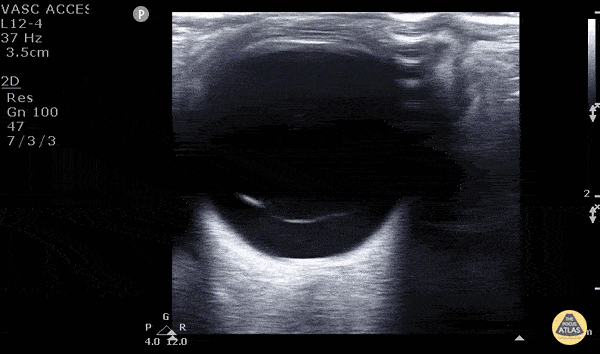

Orbital - Vitreous Detachment

40 year old male with 6 months of decreased vision from his left eye. No pmh or history of trauma. VA was obviously decreased relative to the contralateral eye. POCUS rapidly revealed a freely floating hyperechoic membrane consistent with vitreal detachment. To differentiate between a vitreous and retinal detachment you must look to see if the membrane is attached to the hypoechoic optic nerve. The retinal is continuous with the optic nerve therefore stays attached to the optic nerve in a retinal detachment. A vitreous detachment would be completely untethered as seen in this image. You can also see the “washing machine sign” better pictured in other images in this gallery. Matt Riscinti, MD Bryan Flores, MD - Kings County Emergency Medicine